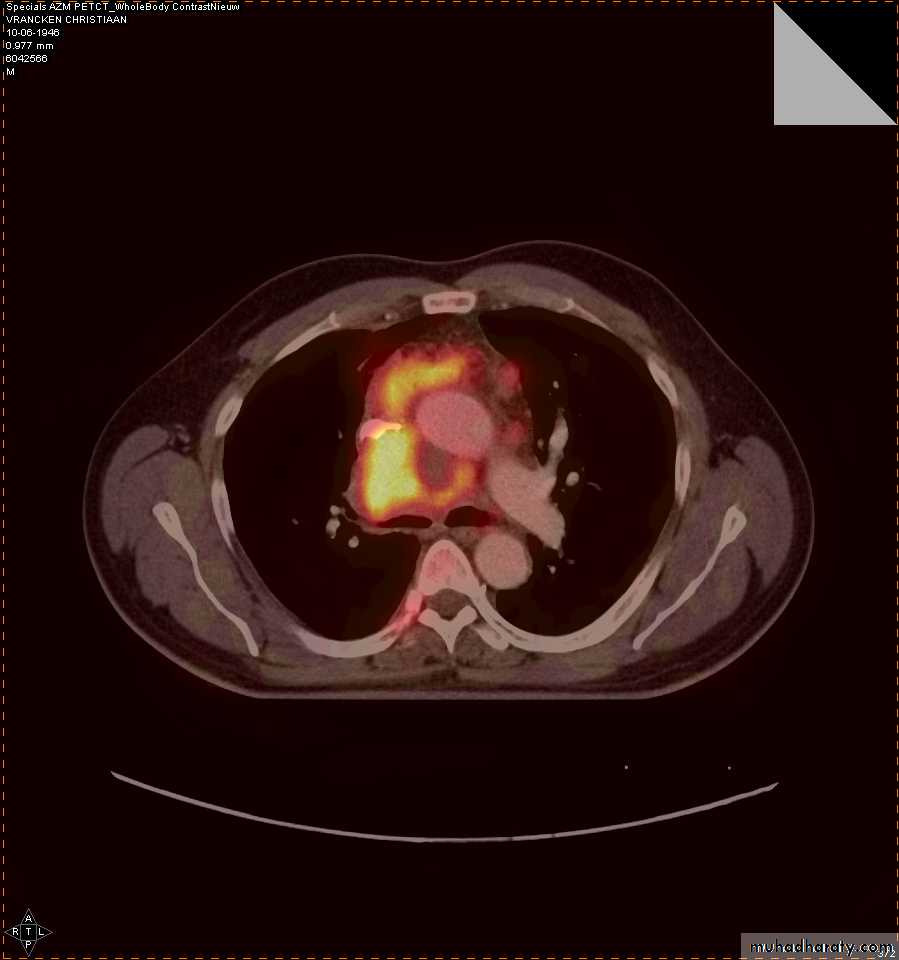

4-PET CT SCAN: its main indication in diagnosis of tumor recurrence after treatment, by demonstrating of increased metabolic level in abnormal tissue. majority of malignant tumors show a greater uptake of the radioactive tracer.

PET

CT

PET/CT

Data UMC Maastricht